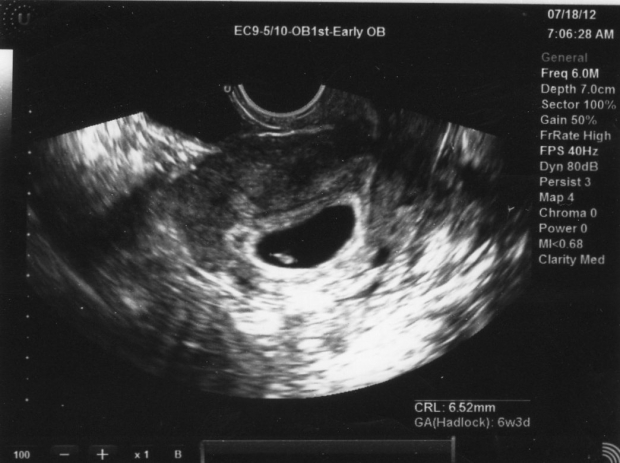

УЗИ на 3 неделе беременности

На 3-4 неделе беременности ультразвуковое исследование выполняется с использованием специального трансвагинального датчика. Эта процедура позволяет уже на таком раннем сроке определить, как протекает беременность, а также выявить возможное внематочное развитие. Кроме того, исследование помогает врачу оценить состояние внутренних слоев матки – миометрия и эндометрия.

С помощью УЗИ специалисты могут на ранних сроках обнаружить такую патологию, как пузырный занос. Симптоматика этого состояния во многом схожа с признаками беременности, однако эмбриона в матке нет. Вместо него наблюдаются пузырьки, количество которых постоянно увеличивается.

При нормальном течении беременности на 3-4 неделе УЗИ показывает значительное утолщение слизистой оболочки матки. В некоторых случаях может быть диагностирована гиперплазия, то есть избыточная толщина, но это явление не представляет опасности и не должно вызывать беспокойства у будущей мамы.

На данном этапе эмбрион еще не виден, он выглядит как крошечная белая точка в полости плодного яйца. Однако УЗИ четко фиксирует желтое тело, которое в этот период обеспечивает гормональную поддержку беременности. Оно функционирует в таком режиме до тех пор, пока не образуется полноценная плацента.

Вы можете ознакомиться на нашем сайте с УЗИ по неделям беременности, где представлены фотографии, иллюстрирующие моменты развития и роста вашего малыша.